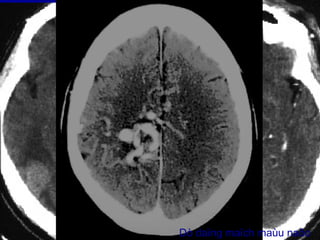

Xuất huyết não thấtXuất huyết não thất

Buøi vaên L., Nam, 45 tuoåi, Xuaát huyeát nhaân beøo-bao trong (P) coù

traøn maùu naõo thaát